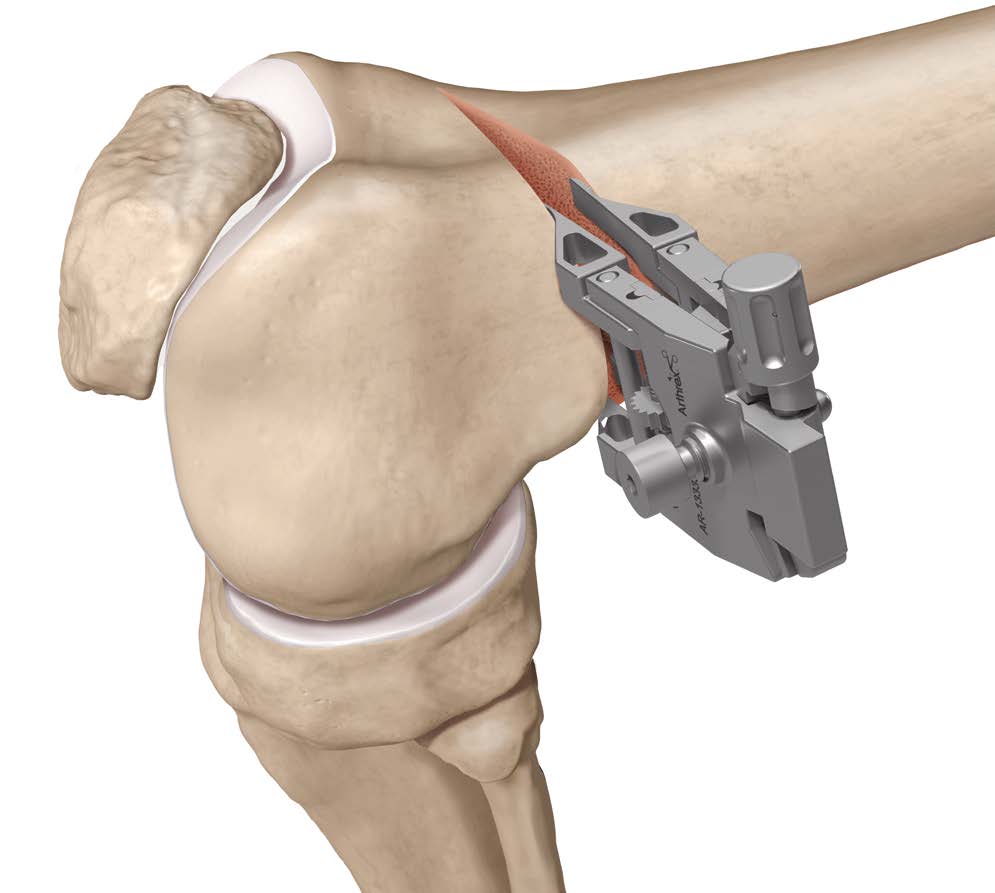

Arthrex ContourLock Distal Femoral Osteotomy Plates

Osteotomy

- insert guide wires

- proximal lateral to distal medial

- proximal 1 - 2 cm above flare of lateral condyle

- aim towards adductor tubercle

- risk of medial hinge fracture reduced if osteotomy at or distal to adductor tubercle

- ensure these are perpendicular to the femoral shaft in the sagittal plane

- above patellofemoral joint and posterior condyles

- stop osteotomy 1 cm short of medial cortex